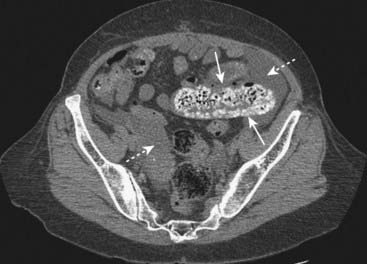

Figure 14-7 Partial small bowel obstruction.

Coronal-reformatted CT scan with oral contrast shows dilated and contrast-containing loops of small bowel (solid white arrows). Although there is still air present in the collapsed colon (dotted white arrows), the disproportionate dilatation of small bowel identifies this as a small bowel obstruction.